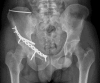

Methods: 7 patients (5 male and 2 female; median age 53 y (25 to 92 y)) with an acetabular fracture were prospectively included. Exclusion criterions were simple wall fractures, cases with anticipated surgical dislocation of the femoral head for joint debridement and accurate fracture reduction. According to the Letournel classification 4 cases had two column fractures, 2 cases had anterior column fractures and 1 case had a T-shaped fracture including a posterior wall fracture.The workflow included following steps: (1) Formation of a patient-specific bone model from preoperative computed tomography scans, (2) interactive virtual fracture reduction with visuo-haptic feedback, (3) virtual fracture fixation using common osteosynthesis implants and (4) measurement of implant position relative to landmarks. The surgeon manually contoured osteosynthesis plates preoperatively according to the virtually defined deformation. Screenshots including all measurements for the OR were available.The tool was validated comparing the preoperative planning and postoperative results by 3D-superimposition.

Results: Preoperative planning was feasible in all cases. In 6 of 7 cases superimposition of preoperative planning and postoperative follow-up CT showed a good to excellent correlation. In one case part of the procedure had to be changed due to impossibility of fracture reduction from an ilioinguinal approach. In 3 cases with osteopenic bone patient-specific prebent fixation plates were helpful in guiding fracture reduction. Additionally, anatomical landmark based measurements were helpful for intraoperative navigation.

Conclusion: The presented prototype planning tool for pelvic surgery was successfully integrated in a clinical workflow to improve patient-specific preoperative planning, giving visual and haptic information about the injury and allowing a patient-specific adaptation of osteosynthesis implants to the virtually reduced pelvis.